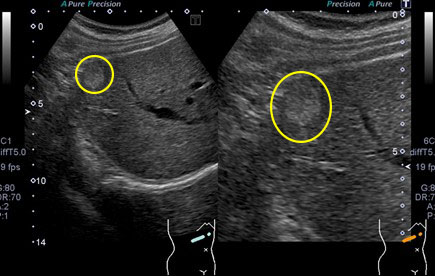

肝血管腫の腹部超音波画像

黄〇内に周囲よりやや高エコー(白い)の円形の腫瘤が見られます。